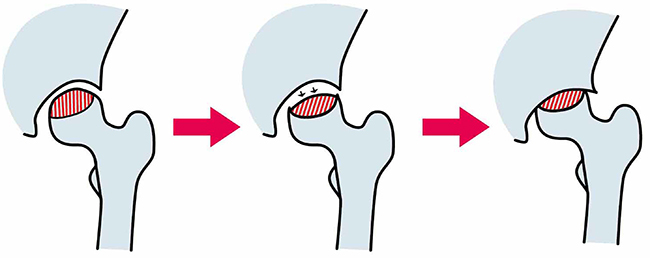

大腿骨頭壊死とは、太腿を支える大きな骨(大腿骨)のうち、足の付け根側の股関節にはまっている部分(大腿骨頭)に血が通わなくなり、骨の組織が壊死してしまう股関節の病気です。

骨の壊死だけでは症状はなく、初期の場合はレントゲン写真などではわからないこともあるため見逃されている例も少なくなく、壊死した骨が体重で押しつぶされて崩れ、大腿骨頭がつぶれてしまった時に突然痛みが現れ気付くケースが多いです。

大腿骨頭壊死は、大腿骨頭に十分な血液が流れず、血が通わなくなって壊死することで起こります。

骨の変形が早い場合や症状が強い場合は、手術を行います。

手術の方法には、自分の骨や関節を残す「骨切り術」と、股関節そのものを人工のものと取り替える「人工関節置換術」があります。

若年者を中心に基本的には骨切り術を第一選択とすることが多く、骨が壊死した範囲が大きい場合や骨が大きく壊れてしまった場合、また高齢者の場合は人工関節置換術を選択することが多いです。